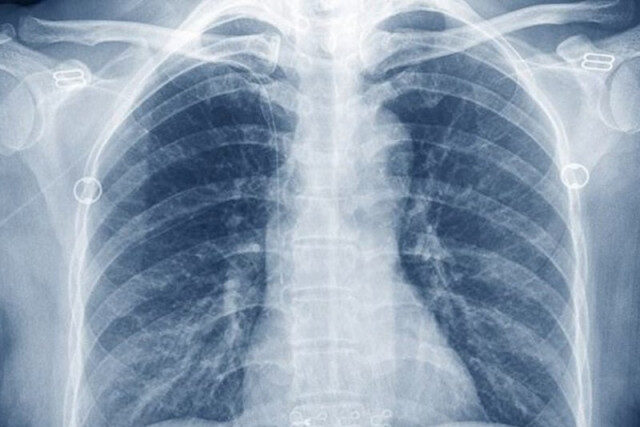

На территории Забайкальского края возникла проблема с сульфатом бария. Это вещество необходимо для проведения контрастного рентген исследования желудка и кишечника.

В пресс-центре местного министерства здравоохранения признали, что препарат внесен в список дефектурных, то есть, временно отсутствует.

«На территории России приостановлено производство данного препарата. Бария сульфат включен в перечень дефектурных препаратов. В связи с этим просим вас направить запрос на заводы-изготовители», — цитирует слова представителей минздрава портал «Чита.Ру».

Вместе с тем чиновники добавили, что рентгеноскопию следует считать всего лишь дополнительным методом исследования и что в лечебных учреждениях Забайкалья можно пройти другие процедуры и осуществить полную диагностику ЖКТ.

К слову, на протяжении последних шести лет на фармрынке в России был представлен только один препарат. После прекращения его выпуска в ноябре 2025 года компания-производитель заявила, что для возобновления работы ей необходимо получить документы. Предполагалось, что это произойдет в декабре.